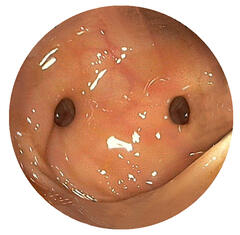

Eine Magen- oder Darmblutung ist ein häufiges Krankheitsbild. Meist blutet es im oberen Verdauungstrakt, d.h. im Magen, in der Speiseröhre oder im Zwölffingerdarm, es kann aber genauso im restlichen Dünndarm oder Dickdarm bluten. Die Ursachen sind sehr vielfältig – Magengeschwüre, Krampfadern der Speiseröhre, Krebserkrankungen, Entzündungen oder auch Gefäßveränderungen sind beispielsweise möglich. Abhängig von der Lokalisation und der Verweildauer des Blutes im Magen-Darm-Trakt, kann es z.B. zum Erbrechen von Frischblut oder zum Absetzen von schwarzgefärbtem Stuhlgang kommen. Eine stationäre Aufnahme ist meistens angebracht. Falls nötig kann der Kreislauf stabilisiert werden. Mittels Magendarmspiegelung kann die Blutung meist gut lokalisiert und behandelt werden.

Bei der Endoskopie kann mithilfe eines Endoskops der Magen-Darm-Trakt, die Gallengänge oder auch die Lunge angeschaut und beurteilt werden. Ein Endoskop ist ein lenkbarer, dünner Schlauch mit einer kleinen Kamera an der Gerätspitze. Des weiteren können mithilfe eines Endoskops auch Gewebeproben (Biopsien) oder Tumorvorstufen wie z.B. Polypen entnommen werden. Für die gesamte Untersuchung wird eine Sedierung angeboten, wodurch der Patient in einem Art Dämmerschlaf ist. Zum Spektrum der Abteilung gehört genauso auch die Ultraschalluntersuchung von außen (Sonographie) und von innen (Endosonographie) dazu – mit der Möglichkeit, Gewebeproben zu entnehmen.